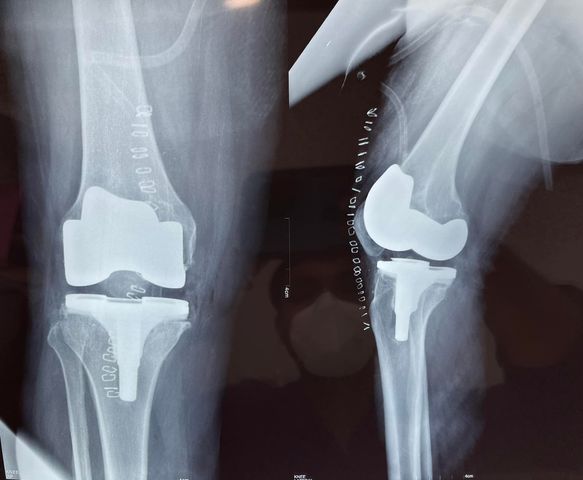

a 64 year old female, this one is special cause the other knee of the patient was operated by one of the best surgeons of kolkata, someone I consider as my teacher, and he set such a high standard of expectation from the patient it was hard to keep up with it

. I was literally asked for oxinium knee and patient controlled analgesia

. But i feel it’s important as a surgeon to meet expectations of the patient however exhaustive it may feel at first glance.